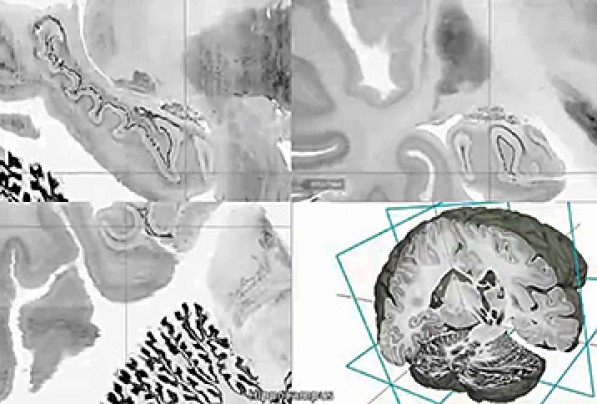

The digital three-dimensional model called "BigBrain" was produced from the thousands of sections made from the brain of a 65-year-old woman. Its resolution is finer than a human hair, so it can reveal clusters of brain. A 65-year-old woman’s brain was cut into 7,400 slices to create the most detailed three-dimensional atlas of the human brain ever made, bringing researchers one step closer to reverse-engineering the brain’s convoluted circuitry. Brain atlases are essential reference tools for researchers and physicians, to determine which areas are “l(fā)ighting up” during a task or thought process, or during image-guided surgery. The better the atlas resolution, the better doctors can target ever-smaller parts of the brain and their individual function. The atlas creators, who are from Canada and Germany, have made the ultrahigh-resolution model — 50 times more detailed than a typical scan — publicly available in a free online format. The authors also published their work in the journal Science on Thursday. The atlas, called BigBrain, offers a common basis for open, worldwide scientific discussion on the brain, said author Karl Zilles of the Heinrich Heine University Düsseldorf. Zilles pointed to a novel treatment for Parkinson’s disease called deep brain stimulation, where electrical impulses are sent through electrodes implanted into specific points in the brain. He said BigBrain may open the doors for more accurate localization of electrode placement and thus render treatment more effective. After staining and digitizing the thousands of plastic-wrap-like slices, the nearly cellular resolution map revealed the network of layers, fibers and microcircuits of the woman’s brain. While variation exists among brains, across ages and individuals, they have largely the same distribution of brain structures and anatomy, said author Alan Evans of McGill University’s Montreal Neurological Institute. There are “subtle shape changes among individuals,” but all atlases start from one representative brain and go from there. The team was chiefly limited by computing power and capacity. To map the human brain with 1 micron spatial resolution, which has been done for mouse brains, the atlas would take up 21,000 terabytes of data — essentially rendering it impossible to navigate. By comparison, BigBrain, with its 20 micron resolution, comprises about a terabyte of data. Prior MRI-based atlases had resolution of 1 millimeter. Richard Leigh, a Johns Hopkins neurologist, said he’s looking forward to test-driving BigBrain for his research on stroke recovery. With the microscopic detail available, Leigh can see which particular groups of neurons are growing through stroke treatment rather than just a general fuzzy area. Evans was in Seattle on Wednesday working with the Allen Institute for Brain Science. Created by Microsoft co-founder Paul Allen, who has committed $500 million since its start in 2003, the Allen Institute has assembled a less-detailed human brain atlas of its own. BigBrain is part of the European Union’s Human Brain Project that brings together specialists in neuroscience, medicine and computing to decipher the mysteries of the brain. President Obama announced in April an initiative to map the human brain, describing it as a way to discover cures for neurological disease and strengthen the economy. |

據(jù)《華盛頓郵報(bào)》6月21日?qǐng)?bào)道,科學(xué)家成功繪制出有史以來(lái)分辨率最高的3D人腦圖譜。這意味著,研究人員在大腦回路逆向工程方面的研究更進(jìn)了一步。 大腦圖譜是科研人員和醫(yī)生必備的參考工具,通過(guò)圖譜,他們可判定在工作、思維過(guò)程中,或是在圖像導(dǎo)航的外科手術(shù)過(guò)程中,大腦哪個(gè)區(qū)域在變化。圖像分辨率越高,醫(yī)生就能更好地聚焦大腦微小的部位,研究它們各自的功能。 加拿大和德國(guó)的研究人員制作了這份大腦圖譜,并于6月19日在《科學(xué)》雜志上發(fā)表。他們將一名已故的65歲女性的大腦切成7400片,將切片染色并進(jìn)行數(shù)字化處理,最終生成高清模型,清晰地呈現(xiàn)出這名女性大腦的皮層、纖維和微電路結(jié)構(gòu)。大腦圖譜分辨率比普通掃描的精度高出50倍,并在網(wǎng)上對(duì)公眾免費(fèi)開(kāi)放。德國(guó)杜塞爾多夫海因里?!ずD髮W(xué)的卡爾·齊勒斯稱,該圖譜名叫“大腦”(BigBrain),它為在世界范圍內(nèi)公開(kāi)對(duì)大腦進(jìn)行科學(xué)討論提供了基礎(chǔ)。 齊勒斯指出,帕金森綜合癥有一種新治療方法叫“深部腦刺激”,該方法通過(guò)植入大腦特定部位的電極輸出電脈沖。他說(shuō),“BigBrain”能使電極植入的部位更精確,使治療更有效。 麥吉爾大學(xué)蒙特利爾神經(jīng)學(xué)研究所的艾倫·埃文斯稱,由于年齡和個(gè)體不同,大腦也會(huì)有所不同,但人腦的結(jié)構(gòu)有很大的共性。大腦“因個(gè)體不同會(huì)有微妙的形態(tài)變化”,但萬(wàn)變不離其宗。 這個(gè)研究團(tuán)隊(duì)受到計(jì)算機(jī)能力和容量的局限。研究人員曾繪制分辨率為1微米的老鼠大腦圖譜,但如果要繪制同樣精確的人腦圖譜,將占用2.1億億字節(jié)的數(shù)據(jù)空間,基本不可能用來(lái)作圖像導(dǎo)航。相比之下,“BigBrain”的分辨率是20微米,約占1萬(wàn)億字節(jié)的空間。而此前磁共振成像(MRI)繪制的大腦圖像精度是1毫米。 約翰·霍普金斯大學(xué)神經(jīng)學(xué)家理查德·利表示,他期待將“BigBrain”用于他的中風(fēng)康復(fù)研究。有了更清晰的大腦微觀圖像,利就可以觀察到,在中風(fēng)治療期間,哪些特定的神經(jīng)元簇有所生長(zhǎng),這比看起來(lái)模糊一片要好得多。 埃文斯6月19日在美國(guó)西雅圖和艾倫腦科學(xué)研究所一起工作。2003年,微軟公司的創(chuàng)始人之一保羅·艾倫出資5億美元,聯(lián)合建立了艾倫腦科學(xué)研究所。目前,該研究所已繪制了自己的人腦圖譜,但是分辨率稍低。 BigBrain是歐盟“人腦工程”的一部分,該工程集中了一批神經(jīng)學(xué)、醫(yī)學(xué)和計(jì)算機(jī)領(lǐng)域的專家,欲破解大腦之謎。今年4月份,美國(guó)總統(tǒng)奧巴馬曾宣布了一項(xiàng)大腦圖譜工程,他認(rèn)為,該計(jì)劃可以找到治愈神經(jīng)疾病的方法,還可以振興美國(guó)經(jīng)濟(jì)。 相關(guān)閱讀 巴黎印發(fā)游客服務(wù)手冊(cè) 旨在改善排外形象 斯諾登曝美國(guó)國(guó)家安全局曾密集攻擊清華大學(xué) (翻譯:聞竹 編輯:Julie) |